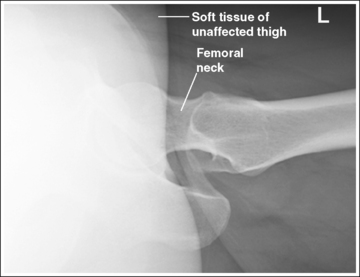

See Figure 7-15 and Box 7-4.

Scatter radiation is controlled. The proximal femur demonstrates uniform density across it.

• Tight collimation and placement of a flat lead contact strip or the straight edge of a lead apron over the top, unused half of the IR, as shown in Figure 7-16, also prevent scatter radiation from reaching the IR.

The femoral neck is demonstrated without foreshortening. The proximal aspects of the greater and lesser trochanters are demonstrated at approximately the same transverse level.

• An axiolateral projection of the hip is obtained by placing the patient on the imaging table in an AP projection, with the unaffected hip positioned next to the lateral edge of the table. Flex the patient's unaffected leg until the femur is as close to a vertical position as the patient can tolerate, and then abduct the leg as far as the patient will allow. Support this leg position by using a specially designed leg holder or suitable support. Flexion and abduction of the unaffected leg move its bony and soft tissue structures away from the affected hip. Inadequate flexion or abduction of the unaffected leg results in superimposition of soft tissue onto the affected hip, preventing visualization of the affected hip (see Image 12).

IMAGE 12

• IR placement. Once the patient's unaffected leg has been positioned, place the grid IR against the patient's affected side at the level of the iliac crest (Figure 7-16). To demonstrate the affected femoral neck without foreshortening, align the x-ray tube horizontally with the central ray perpendicular to the femoral neck and adjust the distal end of the IR until the receptor's long axis is perpendicular to the central ray and parallel with the femoral neck.

• Localizing the femoral neck for central ray alignment. To localize the affected femoral neck, first find the center of an imaginary line drawn between the superior symphysis pubis and the ASIS. Then, bisect that line by drawing a perpendicular line distally (Figure 7-17). This imaginary line parallels the long axis of the femoral neck as long as the leg is not abducted. Once the long axis of the femoral neck has been located, align the central ray perpendicular to it and the IR parallel with it.

The femoral neck is at the center of the exposure field. The acetabulum, femoral head and neck, greater and lesser trochanters, and ischial tuberosity are included within the collimated field. Any orthopedic apparatus should be included in its entirety.

• Center a perpendicular central ray to the patient's midthigh, at the level of the femoral neck, to place it in the center of the exposure field. The center of the femoral neck is located at a level 2.5 inches (6.25 cm) distal to the midpoint of a line connecting the ASIS and superior symphysis pubis. Open the longitudinal collimation the full length of the IR. Transversely collimate to within 0.5 inch (1.25 cm) of the proximal femoral skin line.

• IR placement alternative. The level at which the IR is placed along the patient's lateral body surface determines whether the acetabulum and femoral head are included on the IR. For patients with minimal lateral soft tissue thickness, the upper IR edge should be firmly placed in the crease formed at the patient's waist, just superior to the iliac crest (see Figure 7-17). For patients with ample lateral soft tissue thickness, the upper IR edge needs to be positioned superior to the iliac crest (Figure 7-20). This superior positioning will result in magnification because of the increase in the object–image receptor distance (OID) but is necessary if the acetabulum and femoral head are to be included on the axiolateral hip projection.

Soft tissue from the unaffected thigh is superimposing the acetabulum and femoral head of the affected hip. The unaffected leg was not adequately flexed or abducted.

Flex and abduct the unaffected leg, drawing it away from the affected acetabulum and femoral head. If the patient is unable to adjust the unaffected leg further, the kVp and mAs can be increased to demonstrate this area. A wedge-type compensating filter may also be added to prevent overpenetration of the femoral neck and shaft.